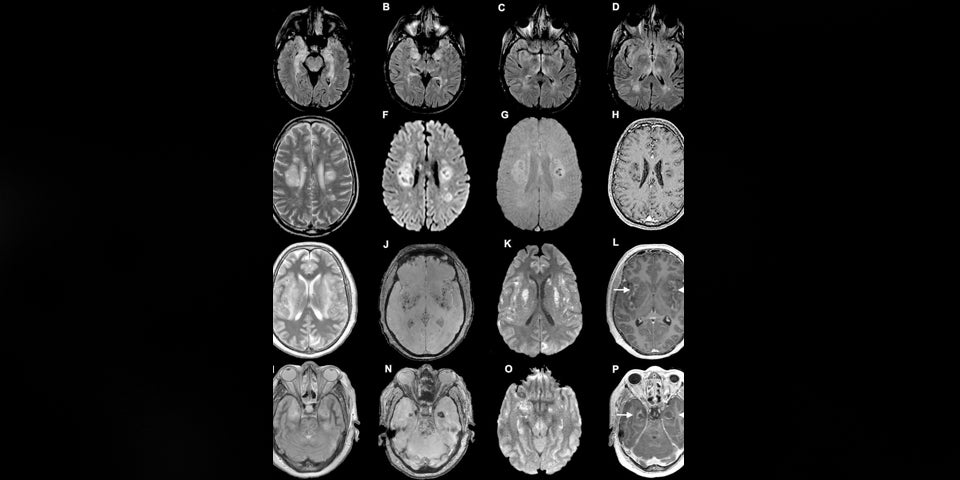

Coronaviren können auch das Gehirn angreifen, wie eine neue Vorab-Studie (noch nicht durch Fachkollegen geprüft) der Universität Yale, berichtet. Das Virus dringe in die Zellen ein und entzieht ihnen den Sauerstoff. Als Folge davon sterben die Zellen ab.

Allerdings komme es relativ selten zu einer derartigen Infektion des Gehirnes, so die Forscher. "Wenn das Gehirn aber infiziert wird, kann das tödlich enden", sagt Akiko Iwasaki von der Yale Universität. Sie forschte mit Kollegen an Gehirnen von verstorbenen Covid-19-Patienten.